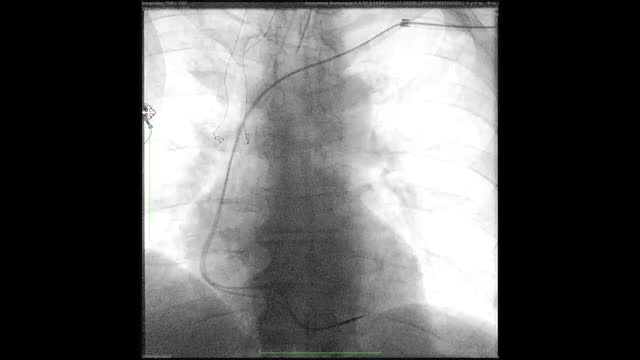

El procedimiento ha de efectuarse siempre bajo control fluoroscópico, siendo igualmente aconsejable la monitorización mediante ecocardiografía transesofágica para la detección precoz de complicaciones cardíacas de la EET (fig. 2).